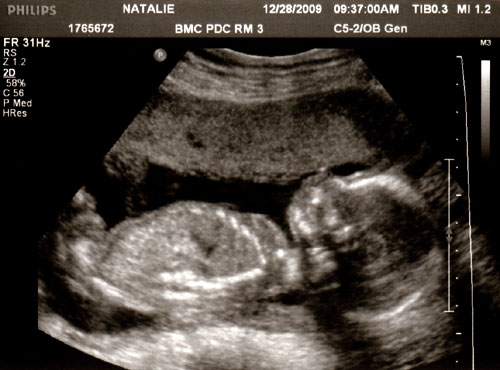

The ultrasound was first thing in the morning, I picked Den up from work on the way in. We both rode in silence for the most part. Nerves and worries flickered through the air. Always the nerves, before an ultrasound. I knew the baby was alive, and that helped tremendously. But what if…? I really just didn’t let my mind go there.

The ultrasound itself was not at all the same as what I remember with Devin. With him I remember just feeling happy at the show. Oh, a leg, an arm! His face! This time I fretted through it all. Is the brain supposed to look like that? Why are they looking so long at the heart? After the ultrasound tech was done the doctor came in to take his own measurements. Again at the heart. Mine hammered away. He pushed in with the probe on my lower right side and then my lower left side, switching back and forth. My pubic bone was in the way, he couldn’t go any lower down. “Just trying to get one last picture,” he said. Until he said, “It all looks good. You’re all set, you can go.” I’ve decided I dislike ultrasounds.

Before the doctor had come in, the tech had moved on to other body parts. Femur, lower legs, feet. Lower legs were crossed when not kicking away. “Come on, baby,” she cajoled, “open your legs.” Back and forth across the lower body. My eyes searched for tell-tale signs. “Looks like a girl!” she said.